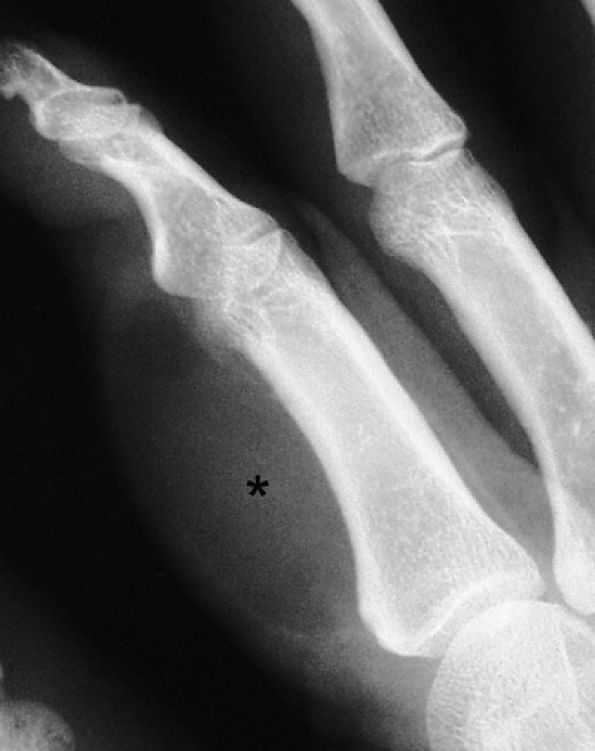

FIGURE 11.82 ● Lipoma of the index finger. Oblique view radiograph shows a low-density palmar mass (asterisk) in the soft tissues.

one third of cases are associated with macrodactyly (macrodystrophia lipomatosa) with bony and soft tissue overgrowth.195